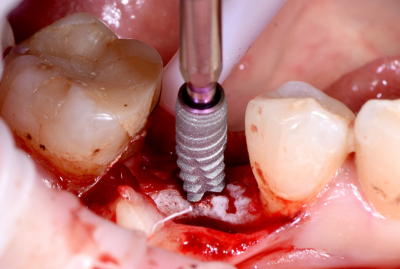

КЛинический случай максима хышова

ОДНОМОМЕНТНАЯ ИМПЛАНТАЦИЯ

Удаление зуба 26. Установка имплантатов VEGA+ в позиции 25 и 27.

✔️ В позицию зуба 27 установлен VEGA+ RV 4.6x10 mm. Получена первичная стабильность 20 Н/см. Установлен винт-заглушка

✔️В позицию зуба 25 установлен VEGA+ RV 4.1x14 mm. Получена первичная стабильность 50 Н/см. Установлен винт-заглушка.